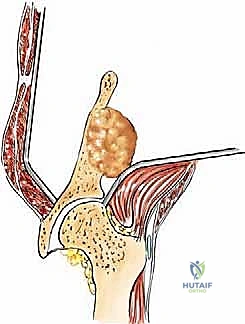

2. عملية إعادة بناء هارينغتون (Harrington Reconstruction)

تُستخدم هذه التقنية المتقدمة عندما يكون الورم قد دمر منطقة "الحُق" (سقف مفصل الورك).

* يقوم الدكتور هطيف بإدخال دبابيس معدنية ملولبة قوية (Threaded Pins) عبر العظم الحرقفي السليم لتصل إلى منطقة الحُق.

* يتم تشكيل كتلة من الإسمنت العظمي حول هذه الدبابيس لإنشاء "سقف صناعي" جديد ومتين لمفصل الورك.

* بعد ذلك، يتم تركيب مفصل ورك صناعي كامل (Total Hip Arthroplasty) يرتكز على هذا السقف الإسمنتي القوي، مما يسمح للمريض بالمشي مجدداً دون ألم.